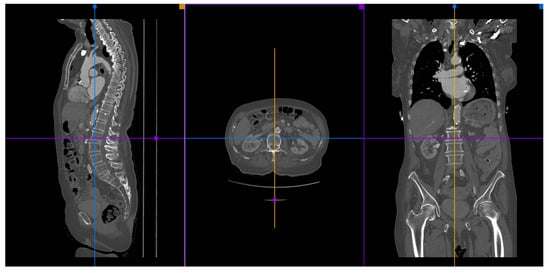

2.7. Peripheral Access Vessels

3.2. Available Methods

3.2.1. Manual Sizing

3.2.2. Semi-Automated and Automated Sizing